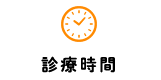

初診時のレントゲン写真からは金属の詰め物の下が大きな虫歯になっていることがわかります。

右の写真の赤い線が虫歯の概形を示しており、緑の線が神経の通っている部屋の概形を示しています。

レントゲン写真からは虫歯と歯の中の神経が近く、虫歯がかなり大きい事がわかります。

- 初診時 レントゲン写真

- 初診時 レントゲン写真